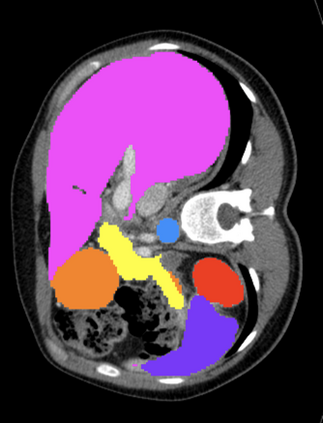

Most recent semantic segmentation methods adopt a U-Net framework with an encoder-decoder architecture. It is still challenging for U-Net with a simple skip connection scheme to model the global multi-scale context: 1) Not each skip connection setting is effective due to the issue of incompatible feature sets of encoder and decoder stage, even some skip connection negatively influence the segmentation performance; 2) The original U-Net is worse than the one without any skip connection on some datasets. Based on our findings, we propose a new segmentation framework, named UCTransNet (with a proposed CTrans module in U-Net), from the channel perspective with attention mechanism. Specifically, the CTrans module is an alternate of the U-Net skip connections, which consists of a sub-module to conduct the multi-scale Channel Cross fusion with Transformer (named CCT) and a sub-module Channel-wise Cross-Attention (named CCA) to guide the fused multi-scale channel-wise information to effectively connect to the decoder features for eliminating the ambiguity. Hence, the proposed connection consisting of the CCT and CCA is able to replace the original skip connection to solve the semantic gaps for an accurate automatic medical image segmentation. The experimental results suggest that our UCTransNet produces more precise segmentation performance and achieves consistent improvements over the state-of-the-art for semantic segmentation across different datasets and conventional architectures involving transformer or U-shaped framework. Code: https://github.com/McGregorWwww/UCTransNet.